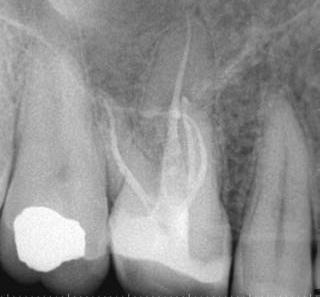

1. a–g. ábrák: A direkt pulpasapkázás lépései. Kiindulási bitewing-felvétel: A meglévő restaurátum közel helyezkedett el a pulpakamrához (a). Kiindulási periapicalis felvétel: Nincs periapicalis elváltozás fennállására utaló jel (b). A pulpaexpozíció (c). A vérzéscsillapítás céljából 20 másodpercen keresztül steril vattagombóccal történő kompressziót követően látható pulpaseb (d). A pulpasapkázás céljából behelyezett anyag, a széli részek tisztázása előtt készült felvétel (e). A röntgenárnyékot nem adó ideiglenes tömés behelyezése után készült felvétel (f). Az első ülés végén a röntgenárnyékot nem adó ideiglenes töméssel ellátott fogról készített röntgenfelvétel (g).

2. ábra: A hat hónapos kontroll alkalmával készített röntgenfelvételen vastag dentinhíd látható a pulpasapkázó anyag alatt.

3. ábra: A hároméves kontroll alkalmával készített röntgenfelvételen megfigyelhető a restaurátum pontos illeszkedése.

A diagnózisunk reverzibilis pulpitis volt. Periapicalis elváltozás jelenlétét nem vélelmeztük. A fogban lévő amalgámtömés eltávolítása során körülbelül egy 3 mm átmérőjű pulpaseb keletkezett a buccalis pulpaszarvnak megfelelően (1. a–g. ábrák) Mivel nem tapasztaltunk jelentős vérzést, és a diagnózisunk reverzibils pulpitis volt, ezért a direkt pulpasapkázás elvégzése mellett döntöttünk.

A kavitást 2,5%-os nátrium-hipoklorit oldattal fertőtlenítettük, majd sűrű konzisztenciájú kalcium-szilikát alapú anyagot (CeraPutty, Meta Biomed) készítettünk elő a direkt pulpasapkázás elvégzéséhez. Az első kezelés végén röntgenárnyékot nem adó ideiglenes töméssel (NexTemp LC, Meta Biomed) zártuk

az üreget annak érdekében, hogy a direkt pulpasapkázásra használt anyag megfelelő pozícióját radiológiailag ellenőrizni tudjuk. A második ülés során kompozit tömőanyagból (Ezfil, Meta Biomed) direkt adhezív restaurátumot készítettünk.

A kezelést követően a beteg tünetmentes volt. A kérdéses fog a kontrollvizsgálatok során végzett szenzibilitástesztekre fiziológiás reakciókat adott. A hat hónapos kontroll alkalmával készített röntgenfelvételen a sérülésnek megfelelően széles dentinhidat észleltünk (2. ábra). A restaurátum a hároméves kontroll során is megfelelőnek bizonyult (3. ábra)